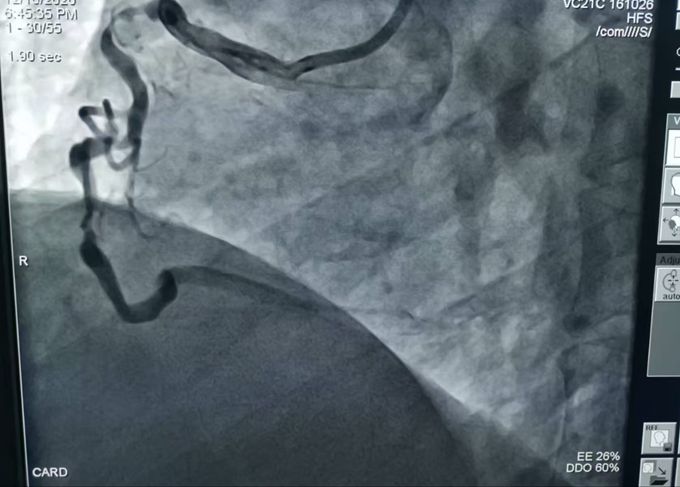

• 3根心臟動(dòng)脈血管嚴(yán)重堵塞 危及生命!十堰人醫(yī)2次手術(shù)為七旬大爺解除“警報(bào)”

3根心臟動(dòng)脈血管嚴(yán)重堵塞 危及生命!十堰人醫(yī)2次手術(shù)為七旬大爺解除“警…

秦楚網(wǎng)-十堰頭條訊?文、圖/記者 秦洪濤 特約記者 馬婷婷 報(bào)道:“當(dāng)時(shí),我們醫(yī)生都有點(diǎn)吃驚,心臟三支主血管均有嚴(yán)重彌漫性鈣化病變且出現(xiàn)不同種度的堵塞,其中兩支最重狹窄為次全閉塞,離急性心肌梗死僅一步之遙,情況十分危急。”近…